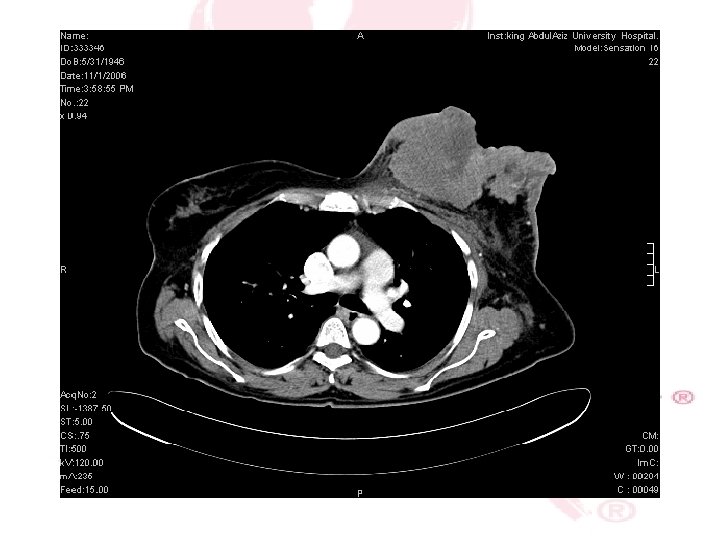

CT SCAN CHEST , ABDOMEN &PELVIS